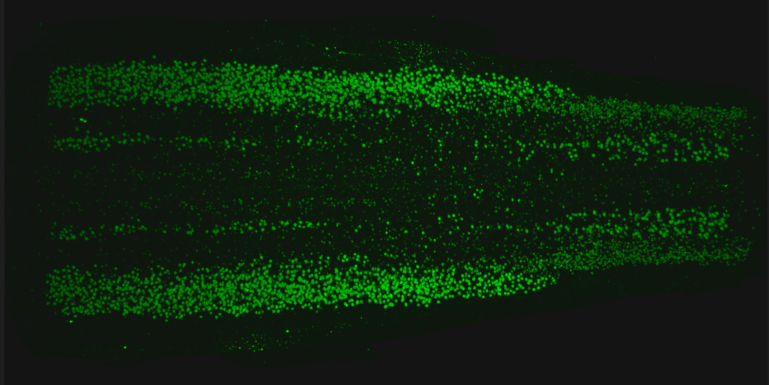

Credit: NICHD/NIH

In a mouse study, National Institutes of Health researchers have identified and mapped a diverse spectrum of motor neurons along the spinal cord. These neurons, which send and receive messages throughout the body, include a subset that is susceptible to neurodegenerative diseases. Created with a genetic sequencing technique, the atlas reveals 21 subtypes of neurons in discrete areas throughout the spinal cord and offers insight into how these neurons control movement, how they contribute to the functioning of organ systems and why some are disproportionately affected in neurodegenerative diseases.

In the current study, the team used a technique called single nucleus RNA sequencing to identify 21 subtypes of spinal cord neurons in mice. The findings reveal highly distinct subtypes, especially among motor neurons that control the glands and internal organs. The team also discovered that visceral motor neurons extend higher up along the spinal column than previously known. The authors believe these motor neurons may be newly discovered subtypes with unknown functions.